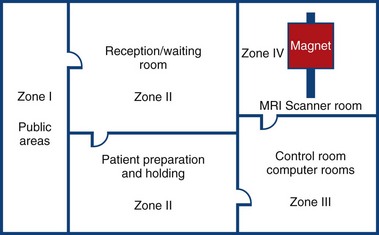

MRI Zone 4

Zone 4: Magnet Room

Authorised access only

The scan room door is always locked when unattended

Metal is removed

Danger signs

When the scan room door is opened, the MRI Safety barrier must be implemented at all times by MRI personnel

Forms for safety and consent

MRI Zone 3

Zone 3: Control Room

All metal removed

Locks on doors

Caution signs

Authorised access only

MRI Zone 2

Zone 2: Patient Screening and Prep

Patients and families undergo screening and are cleared to enter the magnetic area

MRI Zone 1

Zone 1: Unrestricted area (public walkway)